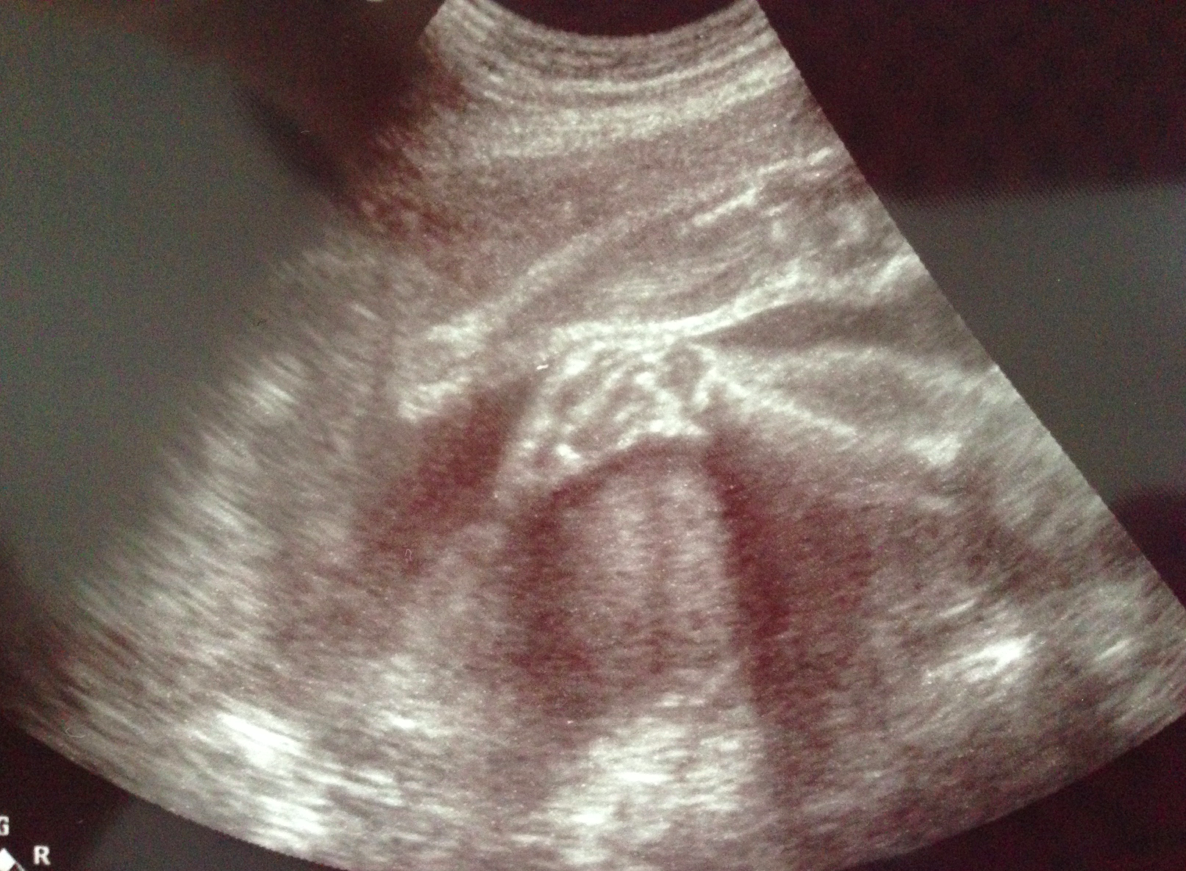

仲有郁郁郁嘅腳仔~睇到我哋都笑咪咪呢~